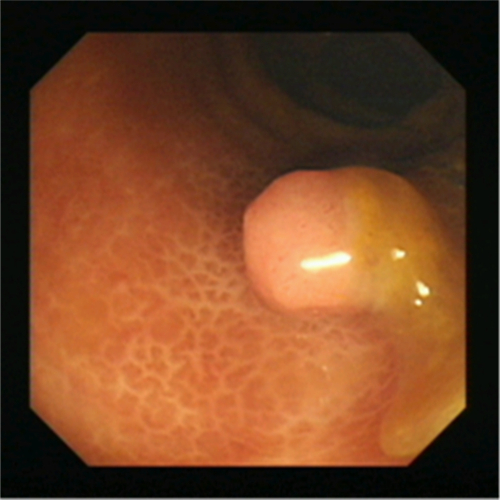

直腸息肉無蒂